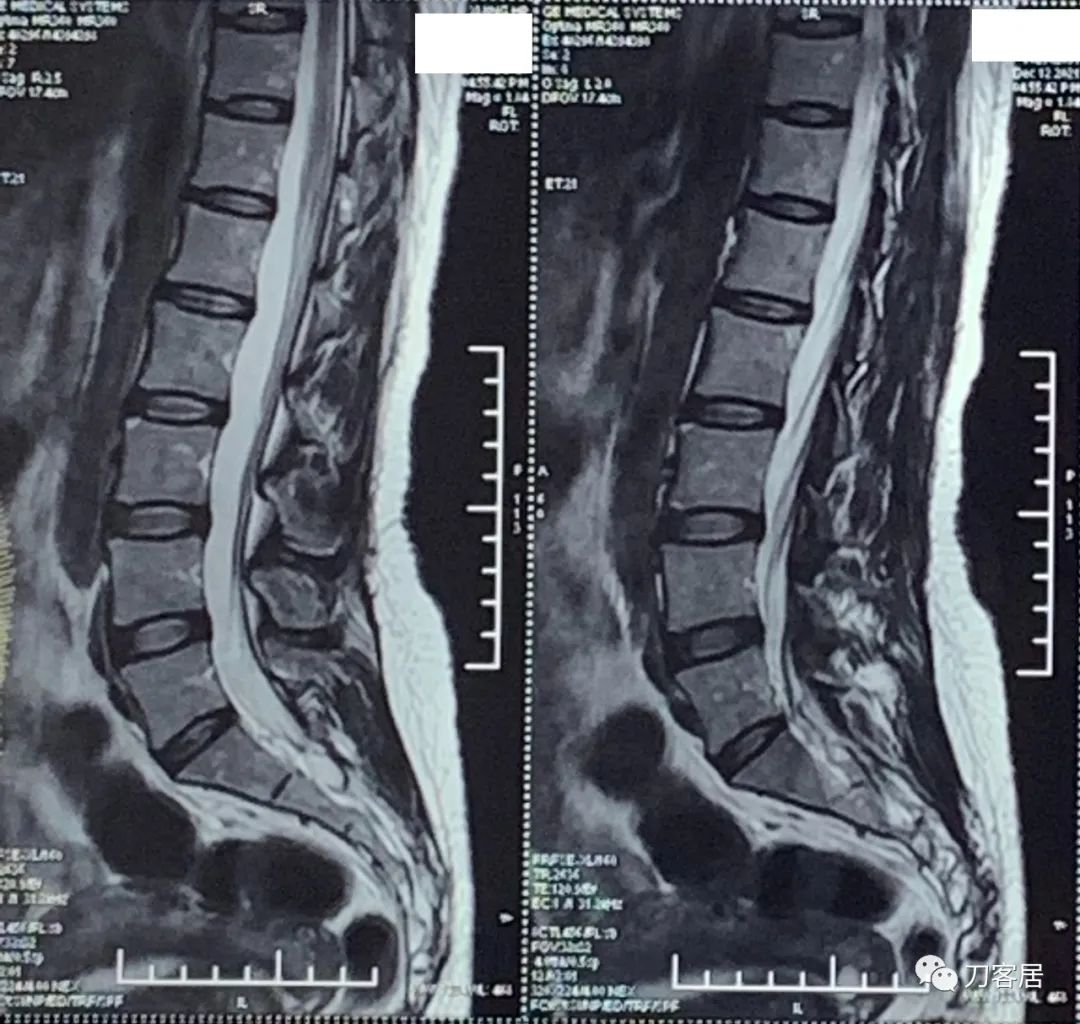

自带腰椎MRI检查未见异常。腰椎X线片提示左侧腰5横突肥大。自带外院骨密度检查结果正常。

20211212西京医院腰椎MRI.